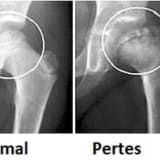

Braxial iflic, körpənin onurğa beyninin boyun səviyyəsindən başlayan sinir strukturlarının uzanması nəticəsində həmin tərəfdə, qolda və əldə müxtəlif şiddət dərəcələrində inkişaf edən əzələ zəifliyi və ya iflicidir.